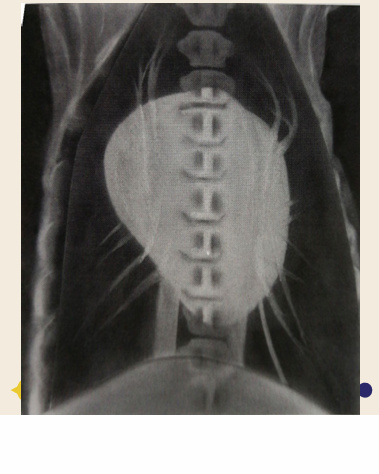

Total situs inversus

Heart is located towards the right side of thorax

Dextrocardia

Mirror image of the thoracic and abdominal organs

Situs inversus